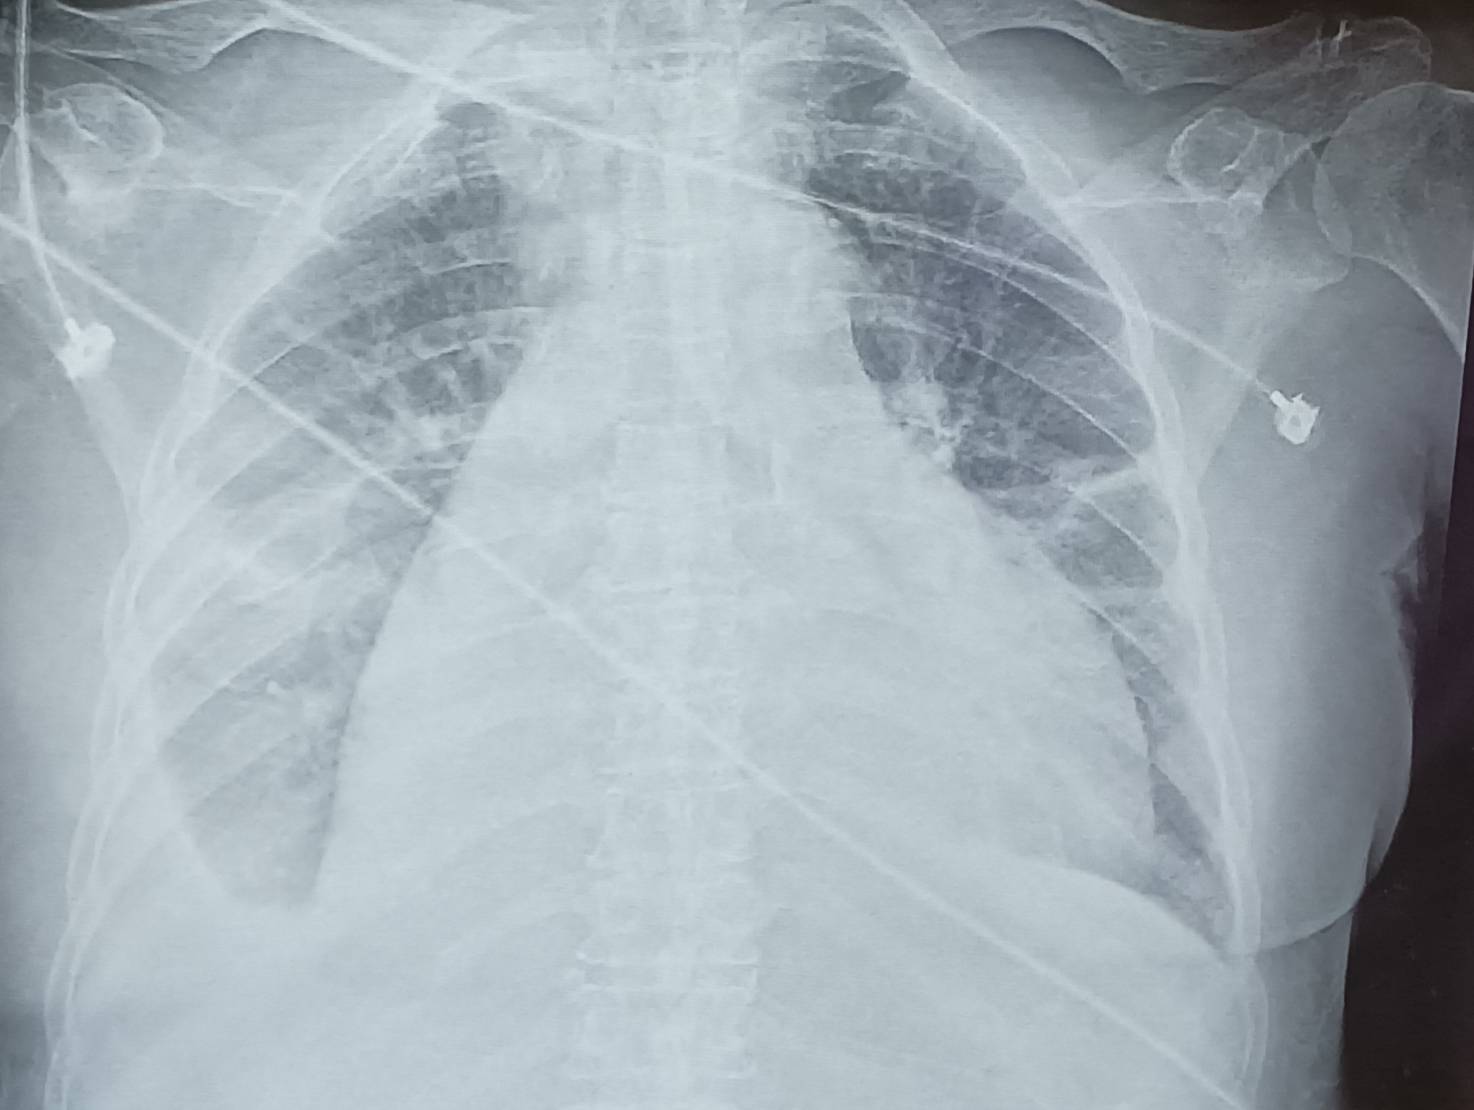

▲個案心包膜積水x光。

(彰化醫院提供)

彰化醫院免疫風濕科主任高堅凱指出,個案有心包膜積水及蛋白尿等病狀,再經抗核抗體檢驗為陽性及血中補體過低,確診為全身性紅斑性狼瘡,目前還在治療中。他說,老年人紅斑狼瘡,因民眾普遍認識不夠及較無警覺心,常會被誤認為只是老化現象,因此常被拖延,走向洗腎或更嚴重的後果。